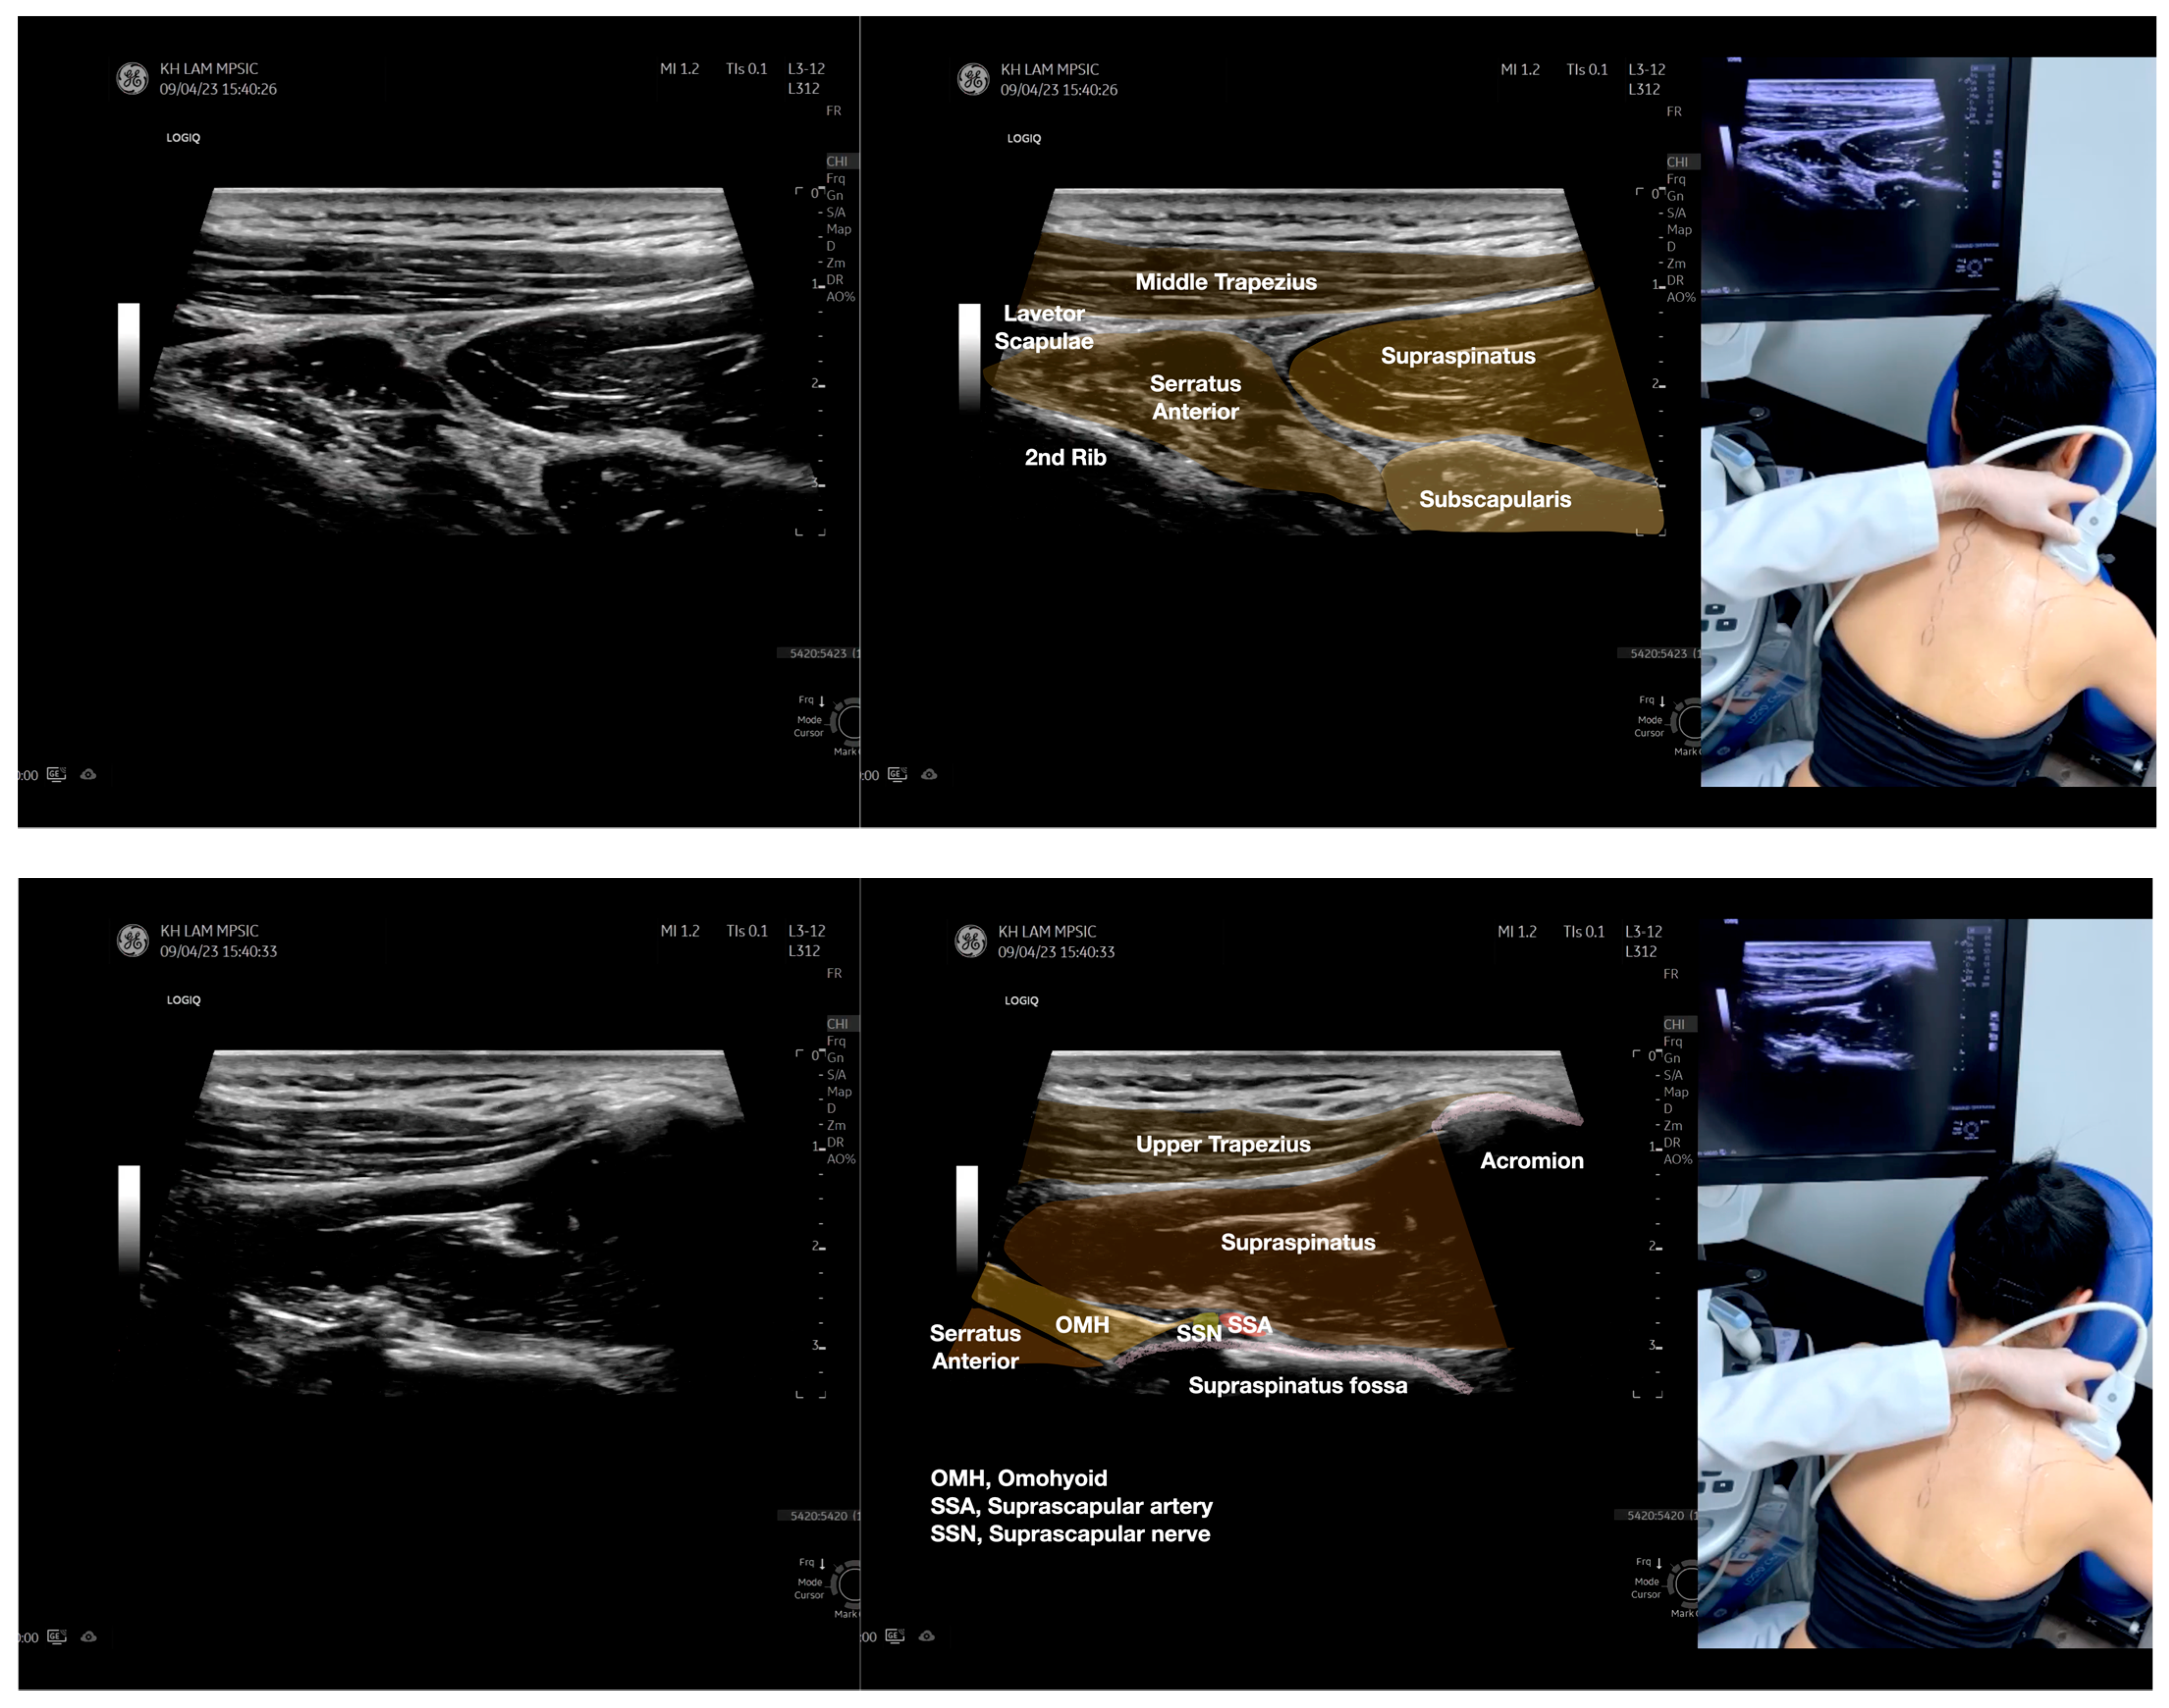

Figure 5.

Sonoanatomy of scanning the infraspinatus fascia in the sagittal plane from the rhomboid minor laterally, then back to the rhomboid major. The step-by-step scanning techniques of the structures illustrated in this figure have been shown in Video S9. Available online: https://www.dropbox.com/s/gu9hhrdq9erin6n/Figure%205.docx?dl=0 (accessed on 1 January 2023).